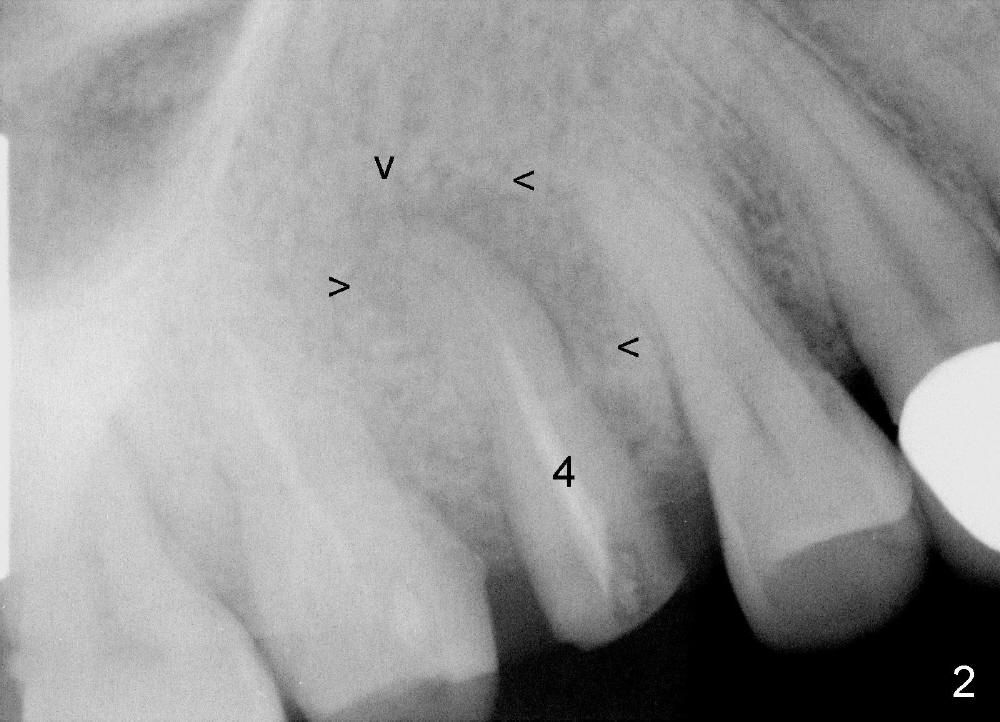

When the tooth #4 is extracted, the apical socket is found to be large with granulation tissue, which is consistent with large periapical radiolucency (Fig.2 arrowheads). The depth of the socket is 17 mm, measured from the gingival margin. The mesiodistal and buccolingual dimensions of the root are 4 and 7 mm, respectively. A tissue-level tapered implant as wide and as long as possible, 4.5x20 mm, is to be placed (Fig.3 (tap drill), 4). The insertion torque is between 35 and 40 Ncm.